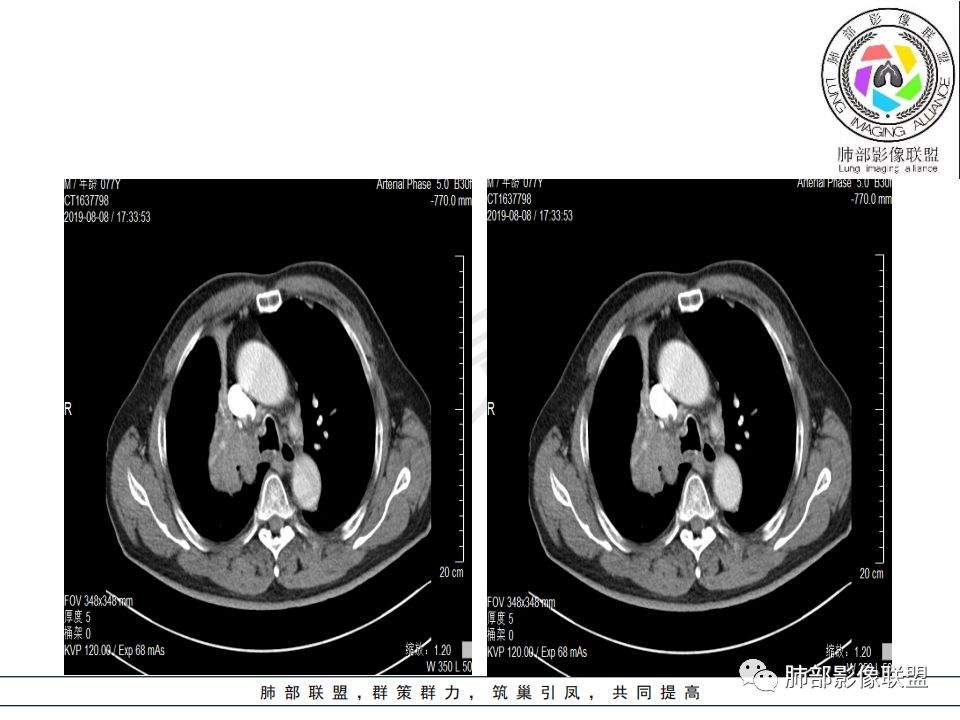

影像:影像右侧大支气管阻塞,临床没有症状或很轻微,要想到胃腺癌转移;胸壁代偿好,透亮度稍低不明显,慢性过程;34.8-52.5HU,主病灶支气管前壁另有1结节,都做成增强两期了,动脉期较平扫有强化;

晨读:患者老年男性,以咳嗽一月就诊,少量白痰,胸CT:纵隔右移,右肺体积缩小,气管下段管壁可见结节样改变,气管软骨变形,气管下段及右主支气管可见新生物向管壁浸润,并向管腔外生长,右上肺肺不张,但不张边缘可见病灶呈膨胀性生长,可见分叶,增强后强化明显。考虑:肺部恶性病变(鳞癌?)

右肺上叶肿块,边缘光滑,略膨隆,近段支气管堵塞,平扫密度均匀,增强后不均匀强化,其内可见不规则血管和坏死,纵隔淋巴结肿大,老年男性,无感染性病史,综合考虑恶性肿瘤(鳞癌,腺癌),鉴别:OP(一般下叶多见)

从强化情况和冠状位看主要还是从外向内的一个肿块,有不张,但不张范围不大,近端支气管堵塞,考虑腺癌或类癌(原发或转移都可能),鉴别鳞癌。

@曹坤,河北保定清苑区人民医院ct室 肿块大,阻塞和不张范围小,强化这么大肿块没有明显坏死,鳞癌这样相对少见了

@刘鋆(福州长乐区医院)影像科 转移啊,腔外都在生长,部分通过支气管壁进入腔内

@刘鋆(福州长乐区医院)影像科 先转移生长到外面,然后进入腔内生长,也是外朝内一种,与平时那种外朝内生长逐渐侵犯近端气管没有太多区别,只不过这个是转移而已。